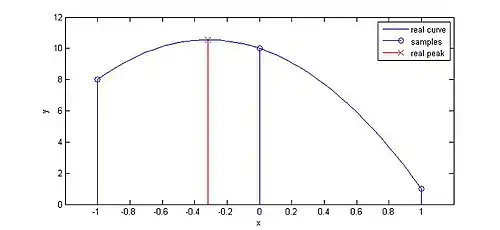

As shown in the right figure, parabolic fit can help find the real peak of the cross correlation function. The equation for parabolic fit in 1D is:[4]

where is the cross correlation function and is the originally found peak. is then used to find the displacement of scatterers after interpolation. For the 2D scenario, this is done in both the axial and lateral dimensions. Some other techniques can be used to improve the accuracy and robustness of the interpolation method, including parabolic fit with bias compensation and matched filter interpolation.[10]